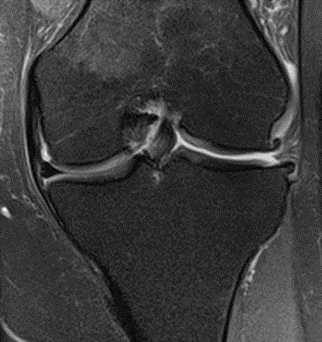

MRI scans illustrating the improvements regarding Group 2 are presented below, showing pre-treatment images with evident cartilage defects, pronounced bone marrow edema, and synovial inflammation, followed by post-treatment scans demonstrating improved joint structure, reduced edema, and decreased inflammation (Figures 12-29).

MRIs of Group 2

Figure 14: Male, 78 years, pre-intervention MRI.

Figure 15: Male of figure 14, two-month follow-up MRI: MSC plus ChondroFiller® liquid.